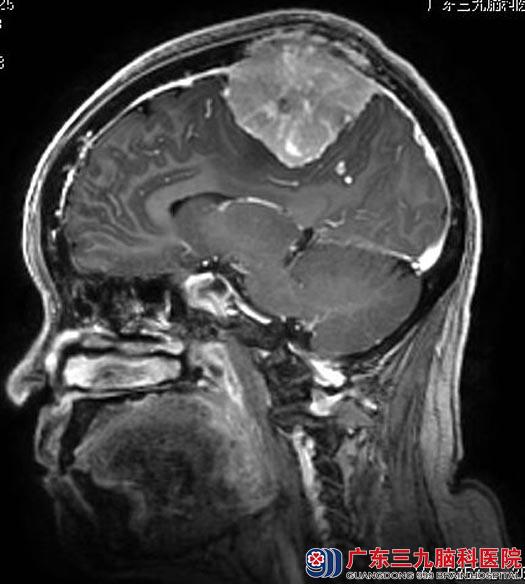

家属联系到广东三九脑科医院综合神经外科鲁明主任。进一步头颅MR检查显示:额顶部镰旁双侧(右侧为主)占位性病变,大小约66.1mm×57.1mm×56.4mm,考虑脑膜瘤可能性大。

▲手术前